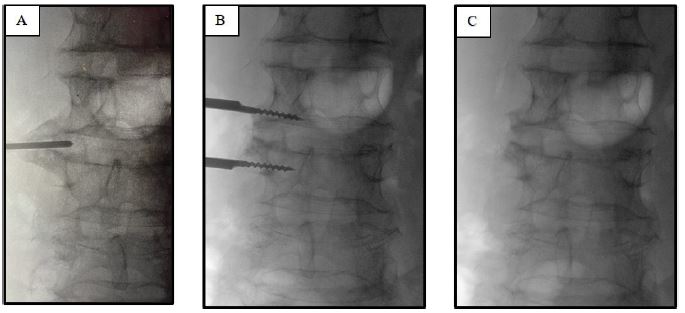

A 72-year-old male patient presented to our institution with a history of right crural neuralgia that had begun a few months prior. At the neurological examination there was no evidence of sensory or motor deficits in the lower limbs, but she experienced significant walking impairment due to intense pain. A spinal lumbar Magnetic Resonance Imaging, MRI, (Figure 1A) revealed the presence of a right lumbar osteophyte at the zygapophyseal joint between the third and fourth lumbar vertebra, resulting in impingement of the ipsilateral psoas muscle. A lumbar CT scan was not performed before the surgery.

Figure 1: Lumbar MRI displaying the right osteophyte the third and fourth lumbar vertebra: coronal (A) and axial planes (B).